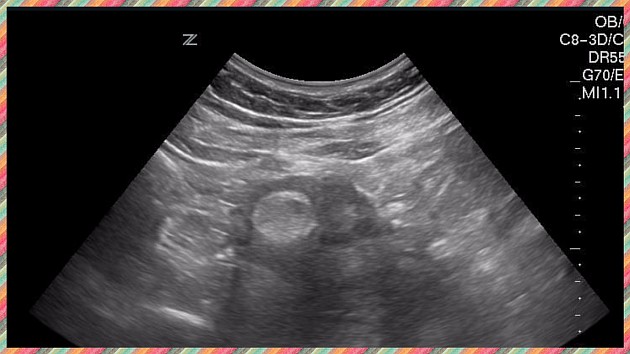

Ультразвуковое исследование брюшной полости.

Квалифицированному врачу отличить симптоматику асцита от ожирения или рака довольно просто, поэтому диагностика проходит быстро. Для подходящего и эффективного лечения ему обязательно необходимо знать причины асцита.